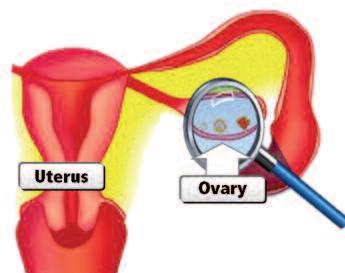

perché alcune forme di cancro sono più frequenti di rispetto ad altre?

La nostra ricerca ha fornito una risposta anche a questa domanda chiave. Il cancro si sviluppa spesso particolarmente negli organi che utilizzano già la digestione del collagene in normali condizioni fisiologiche. Il primo gruppo di organi colpiti sono gli organi riproduttivi. In particolare, gli organi riproduttivi femminili subiscono alterazioni funzionali (ormonali) e strutturali, profonde e ripetute.

In questo capitolo abbiamo già parlato dei profondi cambiamenti del corpo femminile durante l'ovulazione e l'allattamento. In modo analogo l’utero e il collo dell’utero (cervice) sono sottoposte ad una ristrutturazione tessutale, in relazione al ciclo mensile e alla gravidanza, che richiedono un’intensa attività di enzimi che digeriscono il collagene. Non sorprende che questi organi siano i più sensibili ad una demolizione incontrollata del proprio tessuto connettivo e siano, quindi, più esposti al cancro.

Per le stesse ragioni, pure gli organi riproduttivi degli uomini, prostata e testicoli, sono colpiti dal cancro con maggiore frequenza rispetto ad altro organi.

Un altro fattore correlato a questa maggiore incidenza del cancro negli organi riproduttivi femminili e maschili è la loro attività ormonale che stimola la produzione delle collagenasi in questi organi. Livelli ormonali superiori alla norma - prodotti autonomamente dal corpo o causata da somministrazione di farmaci ormonali (contraccezione, terapia ormonale sostitutiva) aumentano il rischio di tumori in questi organi.

Seno

Ovaie

Utero

Cervice uterina

Testicoli

Prostata

Collagenasi usati in condizioni fisiologiche normali

Allattamento

Ovulazione

Maternità

Concepimento

Produzione dello sperma

Produzione del liquido seminale